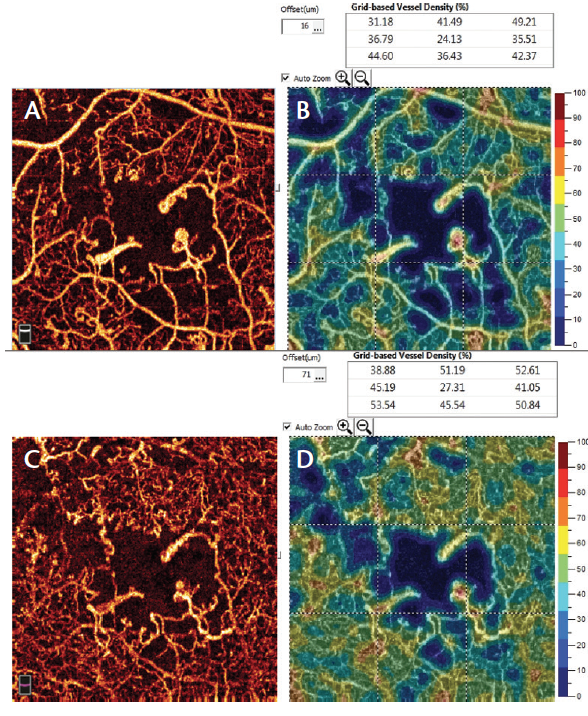

Figure 5. AngioVue imaging (superficial [A] and deep plexus [C] with vessel density quantification [B and D]) of proliferative DR shows areas of nonperfusion, microaneurysms, and clear enlargement of FAZ.

In patients with DR, OCTA demonstrates retinal alterations including capillary dropout in the superficial and deep plexuses, FAZ enlargement, and microaneurysms (Figure 5). The ability to separately examine the superficial and deep capillary plexuses with OCTA helps users to delineate retinal involvement in various diabetic lesions (Video 1). For instance, widening of the FAZ is best seen in the superficial plexus, whereas capillary dropout and microaneurysms are best appreciated in the deep plexus. However, microaneurysms are visible on OCTA only in the presence of intravascular flow; therefore, those with slow flow or thrombosis will remain undetected. The detection of preretinal and prepapillary neovascularization is also facilitated with OCTA, as these new vessels are not blurred by leakage in dye-based angiography.